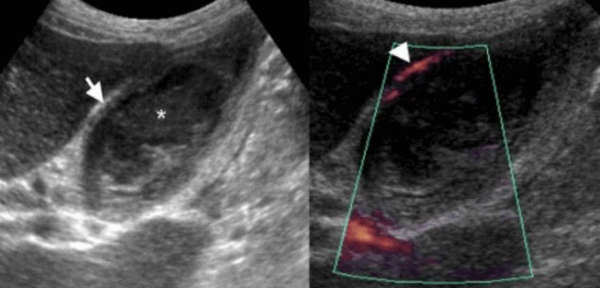

5. УЗИ признаки ксантогранулематозного холецистита:

• Утолщение стенки желчного пузыря, в т.ч. (редко) очаговое и опухолевидное, имитирующее рак

• Гипоэхогенные узлы или тяжи в стенке желчного пузыря

• Повышение эхогенности перихолецистического жира (воспаление тканей около желчного пузыря, отражающих ультразвук)

• Желчные конкременты, сладж, эхогенные включения дебриса в просвете

• Перихолецистические включения жидкости

• Гипоэхогенные участки воспаления паренхимы печени возле ямки желчного пузыря

(Слева) На аксиальной КТ с контрастным усилением у женщины 64 лет с хронической болью в правом подреберье определяется утолщение стенки желчного пузыря и гиподенсные включения в ней. При патоморфологическом исследовании было обнаружено, что эти гиподенсные включения представляют собой зоны некроза, заполненные пенистыми макрофагами. Обратите внимание на усиление перфузии печени (преходящее повышение плотности).

(Справа) На сонограмме у этой же пациентки определяется утолщение стенок желчного пузыря, просвет которого заполнен сладжем, с наличием множественных кистозных участков некроза в передней стенке.